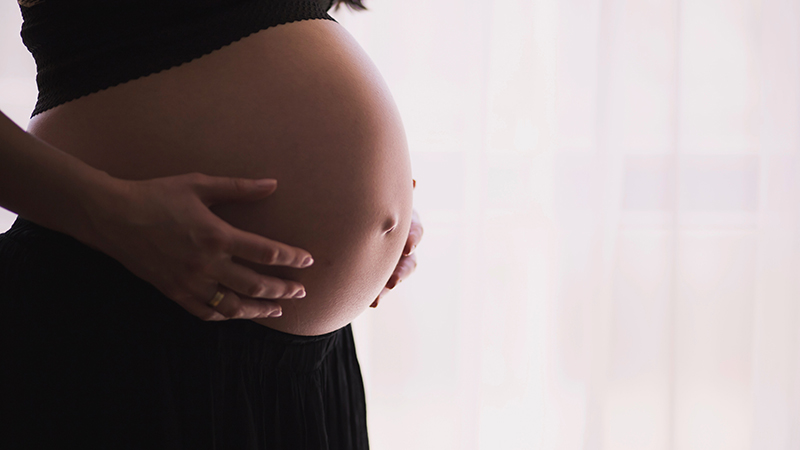

從(cóng)胎兒(ér)第3個(gè)月(yuè)☆Ω開(kāi)始,胎兒(ér)對(duì)鈣的(de)需要(yào)量驟π↕§&然增加,母體(tǐ)低(dī)鈣将直接影(yǐng)★σ響胎兒(ér)的(de)發育。母體(tǐ)缺鈣,孕期會(huì)造成腿抽∞÷筋、流産、難産、骨盆畸形,甚至出現(xiàn)嚴重的(de)産科(kē)ε'₽并發症,嚴重危及胎兒(ér)和(hé)母親的(de)生(shēng)命。為(wφ♥èi)避免以上(shàng)問(wèn)題,孕期的( λde)鈣攝入量為(wèi)每日(rì)800~12♥↓00mg。